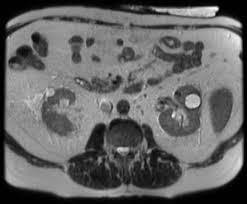

Mri Images Of Kidney Stones - Kidney stones usually originate in your kidneys.